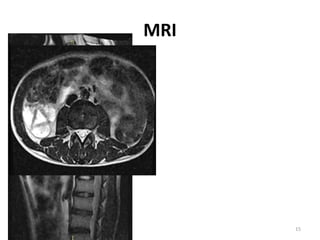

MRI

7/30/2020 15

• #17 Magnetic resonance imaging (MRI) evaluation of the entire spinal cord axis is mandatory in all myelopathic patients. Nb:The classical "owl eye sign" on axial images involving central-anterior cord substance is suggestive of anterior spinal artery syndrome [Figure 1]. Anterior spinal artery syndrome is a rare presentation of acute spinal cord infarction. The etiology is varied ranging from atherosclerosis, vasculitis, surgery, aortic dissection, and acute trauma. It has to be differentiated from spinal multiple sclerosis (MS), the main points of differentiation being the involvement of antero-central cord substance corresponding to the vascular territory of anterior spinal artery and vertical extension over two spinal segments. MS plaques involve peripheral cord substance and seldom extend over two spinal cord segments. [1],[2] Neuromyelitis ophtlmic T1 hypointense follow-up scans may demonstrate cord atrophy and low T1 signal 5 T2 hyperintense (often >3 vertebral body lengths)  central grey matter involvement bright spotty lesions (see above) T1 C+ (Gd) enhancement is common and variable in appearance ring-enhancement seen in a third of patients 17 both on sagittal and axial imaging often ring extends over multiple vertebral levels  patchy "cloud-like" enhancement of the aforementioned T2 bright lesions may be present thin ependymal enhancement similar to ependymitis lens-shaped enhancement on sagittal images 11